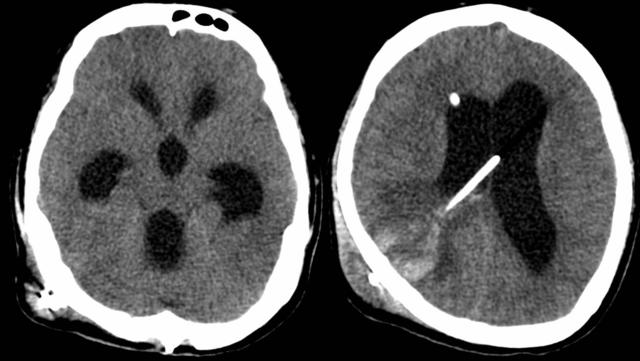

2019-01-24入院时头颅CT

原以为李刚做完脑肿瘤手术后,情况应该会日渐好转,没想到出院10天后,他就出现头痛、呕吐、小便失禁、意识模糊,父母急忙将他送到医院,大脑CT检查提示“脑积水”,2019年1月11日,李刚又接受了脑室腹腔分流手术。手术后复查大脑CT发现分流管穿刺道“颅内出血”,意识状态刚刚有所好转的李刚2天后病情又出现恶化,陷入了昏迷,接着停止了呼吸。医生紧急抢救,穿刺分流管储液阀,抽出血性脑脊液约90ml,李刚自主呼吸逐渐恢复,第二天医生又为李刚做了右侧脑室穿刺置管引流,同时抗感染治疗。

任铭主任分析病情:李刚的头部CT显示颅内血肿稳定,处于吸收期,目前主要问题是梗阻性脑积水明显,颅压高,同时脑脊液化验提示严重颅内感染,二者互相影响可导致恶性循环,如若病情进一步加重将会出现脑疝,危及生命,因此必须保证他脑脊液外引流通畅,降低颅压,而他头上右侧脑室引流管停留时间过长,需要尽快更换。1月28日,任铭主任和雷霆医生为患者行左侧脑室穿刺外引流术+右侧脑室外引流管拔除术,手术顺利。术后继续抗感染和相关治疗。内镜中心的医护团队严密观察患者病情变化,每日多次巡查病房,出现问题及时处理。